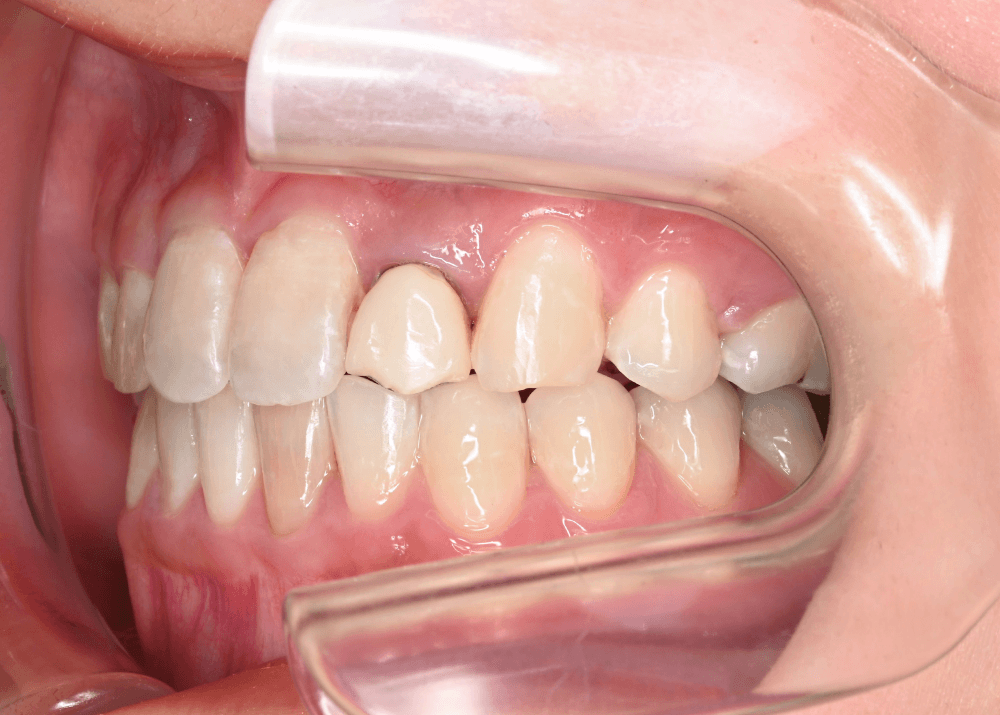

治療前の状態

すでに矯正治療を終えられていたため、歯列に大きなガタつきはなく、上下の歯の咬み合わせも良好でした。

しかし顔貌の観察では以下の特徴が見られました。

側貌(横顔)

上顎前歯が舌側に強く傾斜しており、口唇のサポートが不足していました。

その結果、口元のボリュームが少なく、横顔がやや平坦な印象となっていました。

スマイル時の印象

患者様ご本人も

「笑ったときに歯が奥まって見える」

という違和感を強く感じておられました。

歯並び自体は整っていても、前歯の位置や傾斜によって口元の印象は大きく変化します。

治療前後の写真比較

治療前